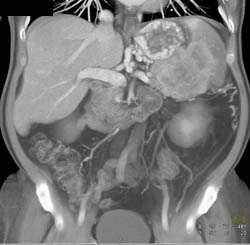

Pancreatic Cancer Occludes the PV/SMV